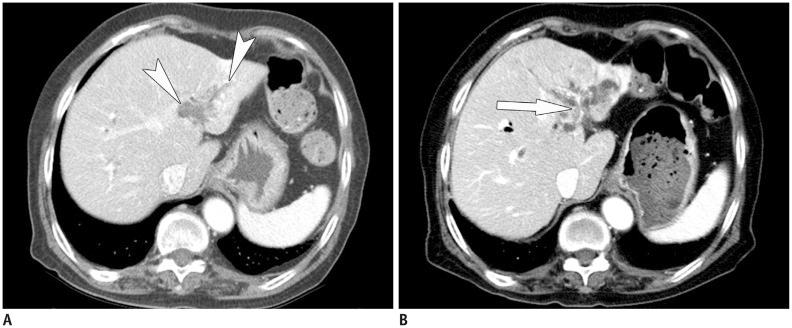

Sclerosing cholangitis is a spectrum of chronic progressive cholestatic liver disease characterized by inflammation, fibrosis, and stricture of the bile ducts, which can be classified as primary and secondary sclerosing cholangitis. Primary sclerosing cholangitis is a chronic progressive liver disease of unknown cause. On the other hand, secondary sclerosing cholangitis has identifiable causes that include immunoglobulin G4-related sclerosing disease, recurrent pyogenic cholangitis, ischemic cholangitis, acquired immunodeficiency syndrome-related cholangitis, and eosinophilic cholangitis. In this review, we suggest a systemic approach to the differential diagnosis of sclerosing cholangitis based on the clinical and laboratory findings, as well as the typical imaging features on computed tomography and magnetic resonance (MR) imaging with MR cholangiography. Familiarity with various etiologies of sclerosing cholangitis and awareness of their typical clinical and imaging findings are essential for an accurate diagnosis and appropriate management.

硬化性胆管炎是一种慢性进行性胆汁淤积性肝病,其特征为胆管炎症、纤维化和狭窄,可分为原发性硬化性胆管炎和继发性硬化性胆管炎。原发性硬化性胆管炎是一种病因不明的慢性进行性肝病。另一方面,继发性硬化性胆管炎有可识别的病因,包括免疫球蛋白G4相关硬化性疾病、复发性化脓性胆管炎、缺血性胆管炎、获得性免疫缺陷综合征相关胆管炎和嗜酸性胆管炎。在本综述中,我们基于临床和实验室检查结果以及计算机断层扫描和磁共振(MR)成像(包括MR胆管造影)的典型影像学特征,提出一种系统性的硬化性胆管炎鉴别诊断方法。熟悉硬化性胆管炎的各种病因并了解其典型的临床和影像学表现对于准确诊断和恰当处理至关重要。